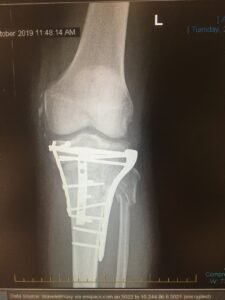

The result was a close call with ‘the reaper’, weeks in hospital, months in recovery, and a left leg with more metal fixings than an Ikea bookshelf. Walking ranges from uncomfortable to agonising, and I have limited bend capability in my left leg.